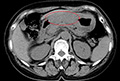

進行がん70代―【手術後リンパ節へ転移、抗がん剤中止】進行がんのため手術で切除したが、リンパ節への転移あり。抗がん剤治療を開始するも、副作用が強く中止。漢方療法と免疫療法でがんはほぼ消失。